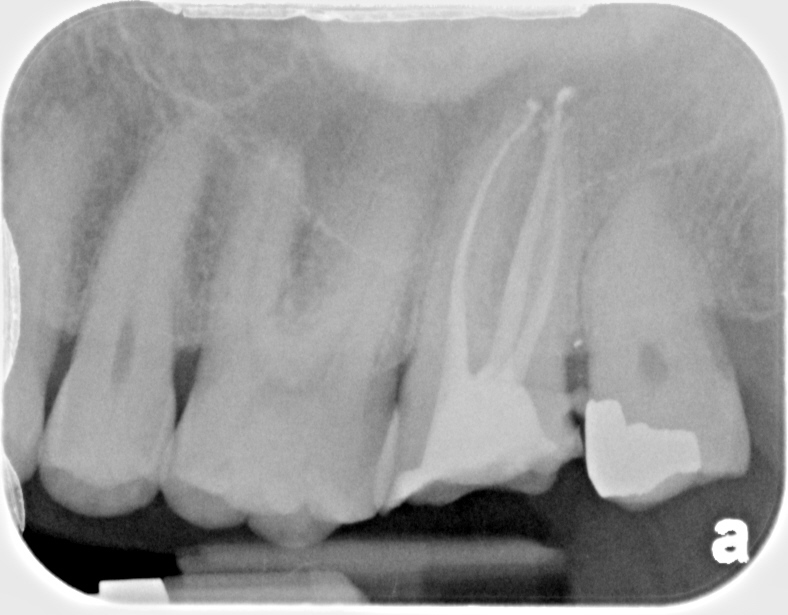

This was taken from old notes and don’t recall exact spacing of MB1/MB2. First one is CaOH next is final. This is before started taking routine angled Pas. Completed in Mendota.